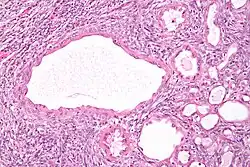

High magnification micrograph of a cystic nephroma showing the characteristic simple epithelium with hobnail morphology, and the ovarian-like stroma. H&E stain.

The characteristics of cystic nephromas are:

• Cysts lined by a simple epithelium with a hobnail morphology, i.e. the nuclei of the cyst lining epithelium bulges into the lumen of the cysts,

• Ovarian-like stroma that has a: